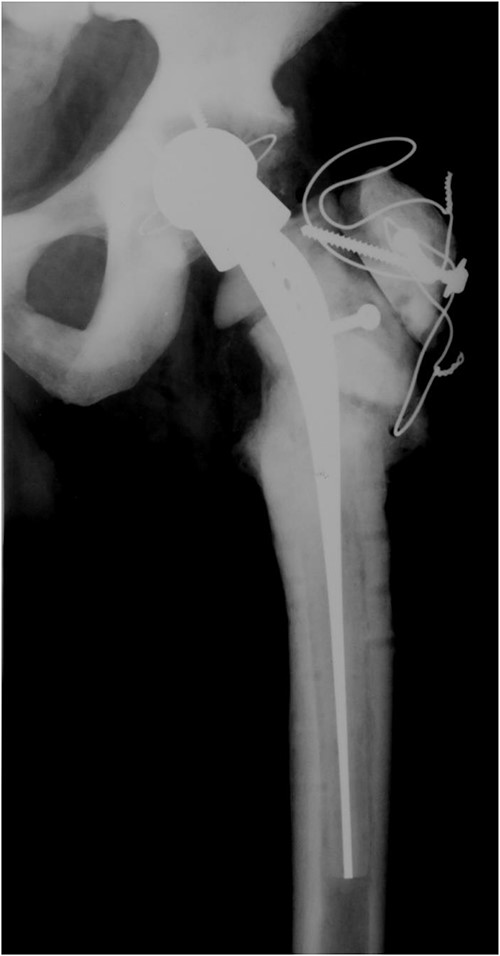

A 73-year-old man showed himself to our hospital in 1989, complaining of left hip pain. X-ray imaging revealed advanced osteoarthritis of the left hip as well as skeletal abnormalities pathognomonic for osteopetrosis. Following earlier intertrochanteric osteotomies carried out elsewhere, there was osteosynthetic material present in the right femur. A cementless isoelastic total hip arthroplasty (THA) was performed (Fig. 1). The greater trochanter was fractured and repaired with screws and cerclages.

Isoelastic uncemented hip arthroplasty. Broken trochanteric part was fixed with cerclage wires and screws.